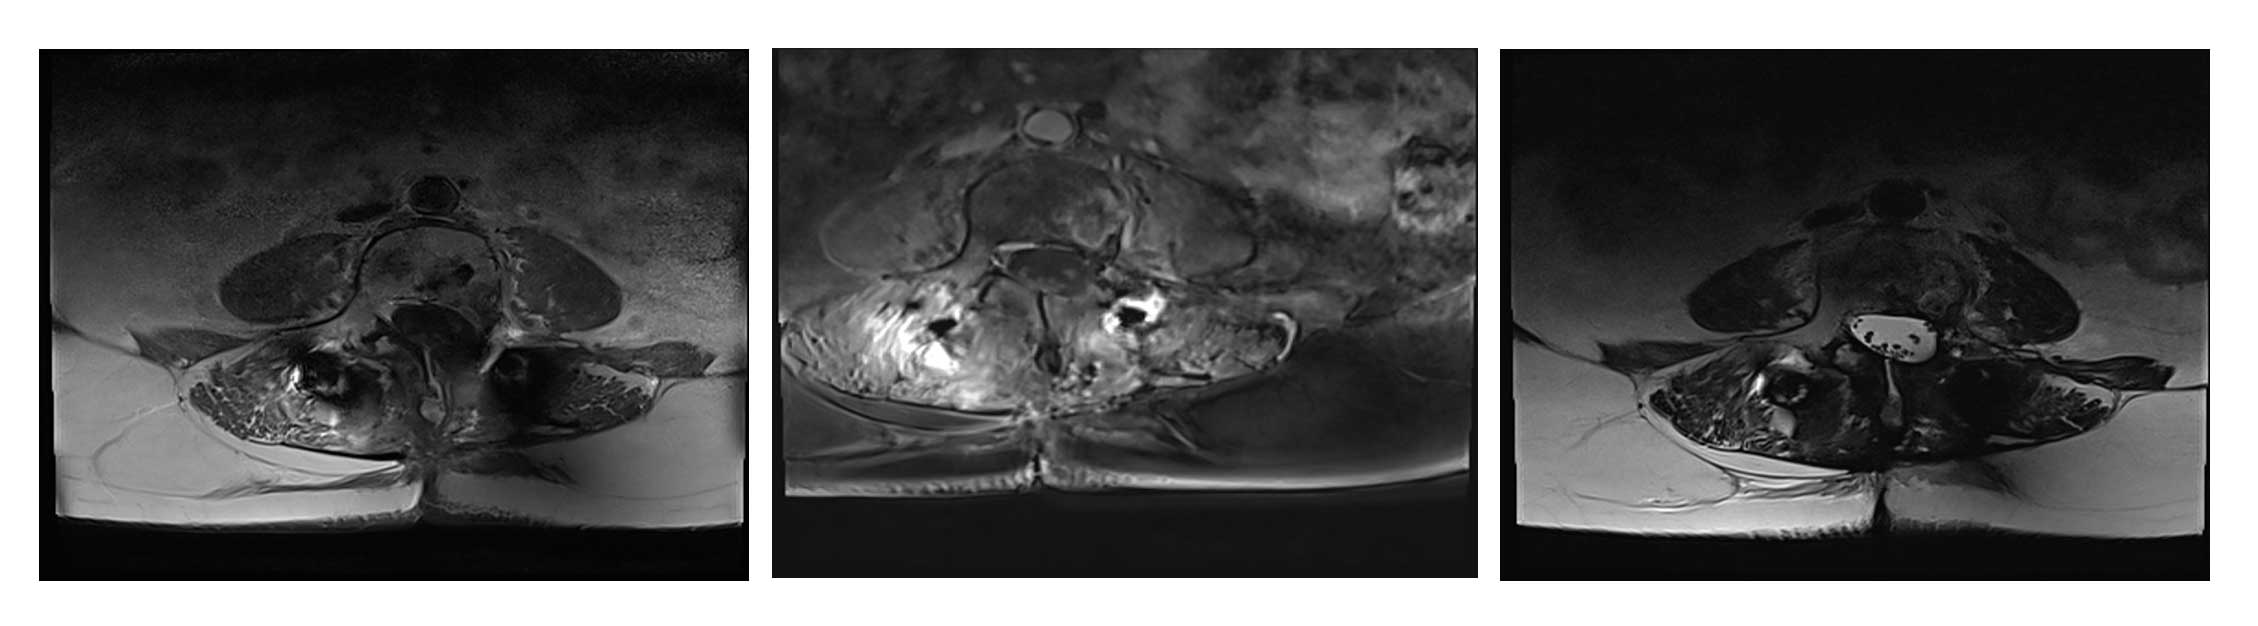

Ameliyat Öncesi: MR’da ek olarak tümör nüksü görülmekte.